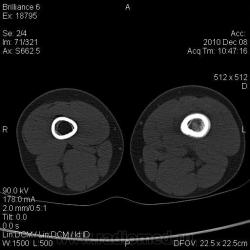

Мальчик 10 лет. Жалобы на боли в н/3 бедра, появились несколько недель назад. Присутствует ночной компонент болей, хотя и не превалирует. При осмотре - хромает на левую ногу, припухлость и болезненность при пальпации в н/з бедра, больше по медиальной поверхности. Выполнили рентгенограммы, затем - КТ, выявлена следующая картина. Мысли самые нехорошие :-(. Завтра делаем открытую биопсию.

хорошего мало,литический очаг, периостит, м\тк компонент вздутие кости, возраст- Юинг? Тут нужна Татьяна Валентиновна

Типичное место, имеется мягкотканный компонент. Да, хорошего мало...

Остеосаркома мне представляется более вероятной, но согласна с Александром Викторовичем - дифференцировать надо с Юингом.

Как ни жаль, но, однозначно, злая опухоль. Я больше склоняюсь к саркоме Юинга.

Остеогенная саркома, за Юинг - нет лука, но довольно крупный компонент в костно-мозговом канале. Надо бы глянуть на МР,, куда улетает по гаверсам и по костно-мозговому каналу. Интересна тактика хирургов. Думаю предложат органсохранную операцию, получат через 6 месяцев рецидив и ждём лёгкие. Сделали-ли сейчас КТ лёгких интересно, если исходно предполагается зло?

Стадирование, конечно, проводили. КТ легких, УЗИ органов брюшной полости - чисто. Заключение гистологов - остеогенная саркома. Направили ребёнка в РДКБ. По предшествующему опыту - сначала проводят несколько курсов химии, а потом - эндопротезирование.